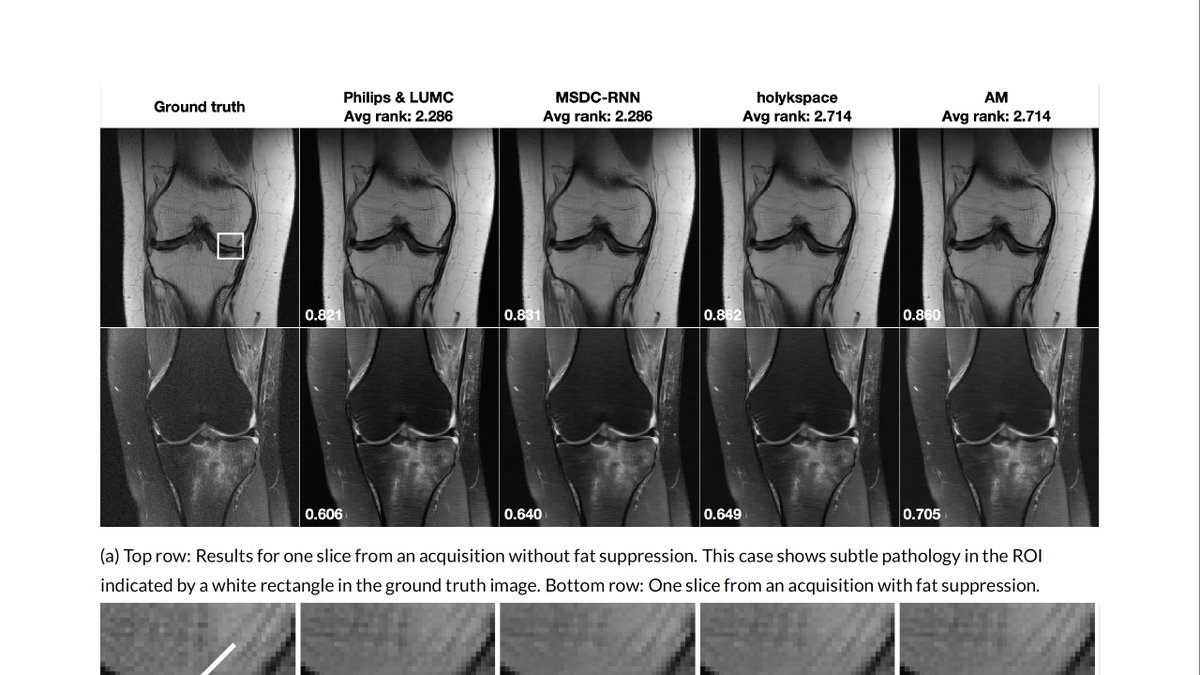

Our imaging scientists, together w/ colleagues at

@facebookai research, discuss the results & lessons of the 2019 fastMRI challenge: [preprint] https://arxiv.org/abs/2001.02518 [leaderboards] https://fastmri.org/leaderboards/challenge …#AI for faster#MRI@tulliemurrell@mattmucklm@DanielSodicksonpic.twitter.com/ugdZieP1ML

Last year, the fastMRI FAIR team and NYU Langone Health held a public competition to advance research in the field of Machine Learning for MR image reconstruction. We just uploaded an arxiv paper with our learnings and results here https://arxiv.org/abs/2001.02518